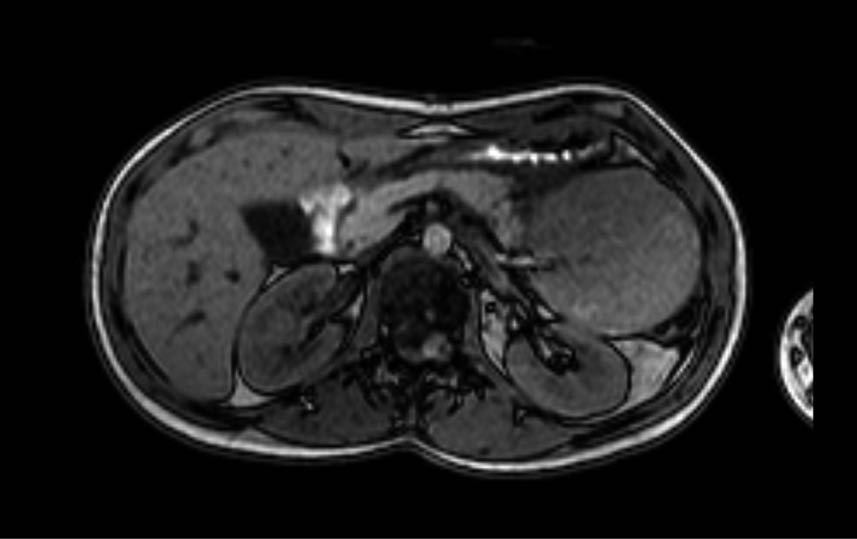

Seröses Zystadenom (SCN) – Abb. 1.A & 2.D

Solid-pseudopapilläre Neoplasien (SPN) – Abb. 1.B

Muzinös-zystische Neoplasien (MCN) – Abb. 1.C & 2.A

Abb. 1A

Abb. 1B

Abb. 1C

Repräsentative Abbildungen zu Bildgebungsverfahren von zystischen Pankreasläsionen: (A) CT-Scan eines serösen Zystadenoms des Pankreas (B) MRT-Scan einer Pankreas-assoziierten solid-pseudopapillären Neoplasie (C) EUS-„Image“ einer intrapankreatischen muzinös-zystischen Neoplasie

Intraduktale papilläre muzinöse Neoplasien (IPMN) – Abb. 2.B/C & 3